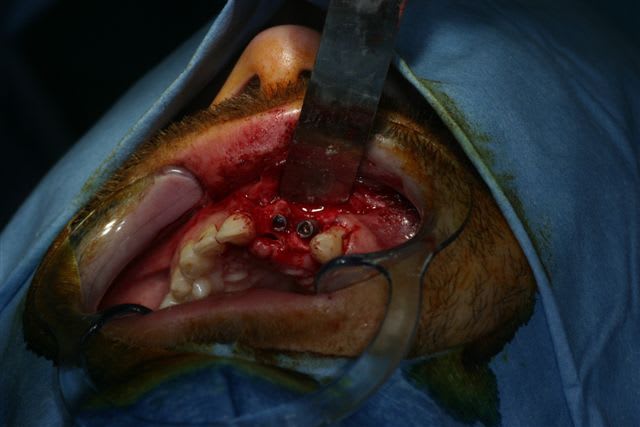

un petit cas ou par chance il y a eu un scan après la pose d'un implant avec bio-oss + mb résorbable juste coincée dans la vis de l'implant avec un point en bretelle, on voit bien le remaniement osseux et l'os néoformé avec un aspect différent au scan

il faut effectivement qu'il y ait un apport trophique, comme il est abscent en vestibulaire à cause de la mb, une cavité où coincer le bio-oss est necessaire avec des parois osseuses et non cementaires